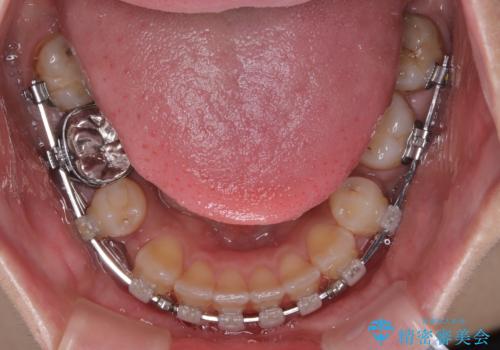

- 矯正装置

- クリアブラケット

- 口元の突出感と奥歯のむし歯を気にして来院された患者様です。

奥歯の虫歯は事前に矯正治療用の仮歯に置き換えて矯正治療を行い、装置除去後にセラミッククラウンにて補綴治療を行うこととしました。

通常は上下左右の第一小臼歯4本を抜歯することになりますが、左側下顎の第二小臼歯は既に根管治療をされており、予後が良くないとのことでこの歯を抜歯し、ワイヤー装置にて矯正治療を行うこととしました。